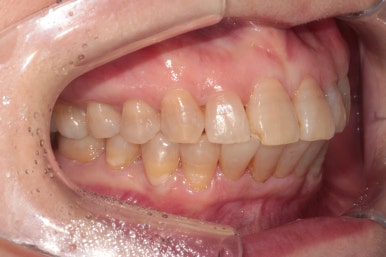

상당히 뻐드러져 있었던 앞니가 적절한 위치를 찾아가고 있는지 확인을 하기 위해 측면 사진도 찍어봅니다.

저희 치과에서는 Overjet이라고 표현하는데, 윗니가 아랫니를 약 1-2mm 정도 덮는 모양이어야 평균이라고 봅니다.

보시면 위와 아래 치아 사이에 약간의 틈이 있는 것을 보실 수 있죠? 점점 개선될거에요!!

성인 앞니 부분교정 2년이 지나고 나서도 변함없이 깔끔하게 유지되고 있는 위턱아래턱 관계를 보실 수 있을거에요. 이렇게 관리 잘 해주시는 분들께 치과의사도 감사함 뿐입니다!

교정유지장치 끊어짐 없이 아주 깔끔하게 잘 관리되고 있습니다.

조금 힘드셨겠지만, 철저한 구강위생보조용품 사용으로 더욱 완벽히 관리해주시고 있는 모습입니다.

보통 교정유지장치가 있는 경우 6개월에 한번씩 내원하셔서 스케일링 받으시길 권해드립니다!!